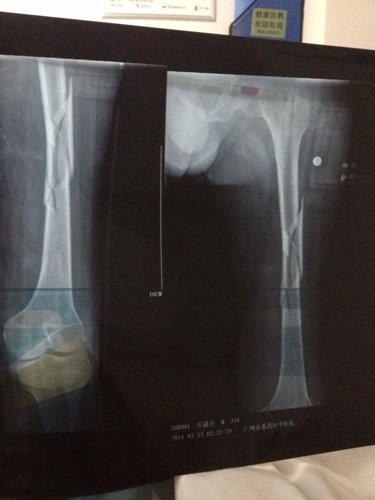

你好医生!左腿原来有小儿麻痹证,就在上个月11号不小心跌倒骨折13号做手术加钢板!现在在家休养。现在腰很痛?是怎么回事,有过性生活。现在简单吃两种药?请问医生像我这种情况会不会很难恢复原来那样?是不是还要吃些什么?还有要不要外敷些什么?还要腰很痛怎么办,谢谢!

病情分析: 图上所见,复位固定都还不错。 指导意见: 骨折的治疗重点是有效牢靠的固定。药物是次要的可以不服。也要注意尽量不要做对愈合不利的活动。除非是肌肉的锻炼等。